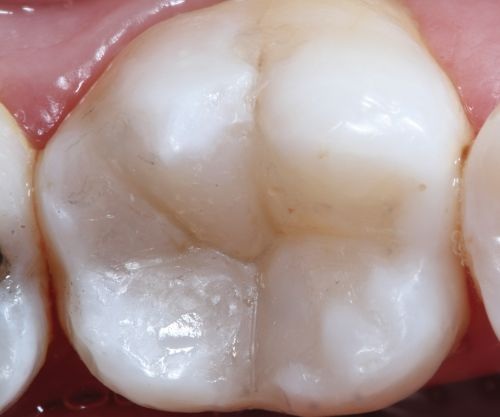

A 35-year-old male presented to the clinic to replace some inadequate restorations, one of which was for the lower right first molar (Fig. 1). For this tooth, the molar was restored with composite resin using the direct technique. The operative field was isolated, the old restoration was removed, and surface hybridization was completed using Futurabond U universal adhesive from Voco (Fig. 2). After placing a sectional matrix and a spacer ring, the composite resin (Voco’s GrandioSO 4U, shade A2) was placed in the proximal box with a thickness less than 4 mm, which is the maximum recommended thickness for the chosen material (Fig. 3). Additional increments of composite resin were applied to complete the anatomical stratification. The final morphology was sculpted, followed by light-curing to ensure complete polymerization (Fig. 4). The rubber dam was removed (Fig. 5), and the occlusion was adjusted using a finishing carbide bur with 12 blades (Fig. 6). Finishing and polishing was completed, with the final result shown in the Figures 7 and 8.